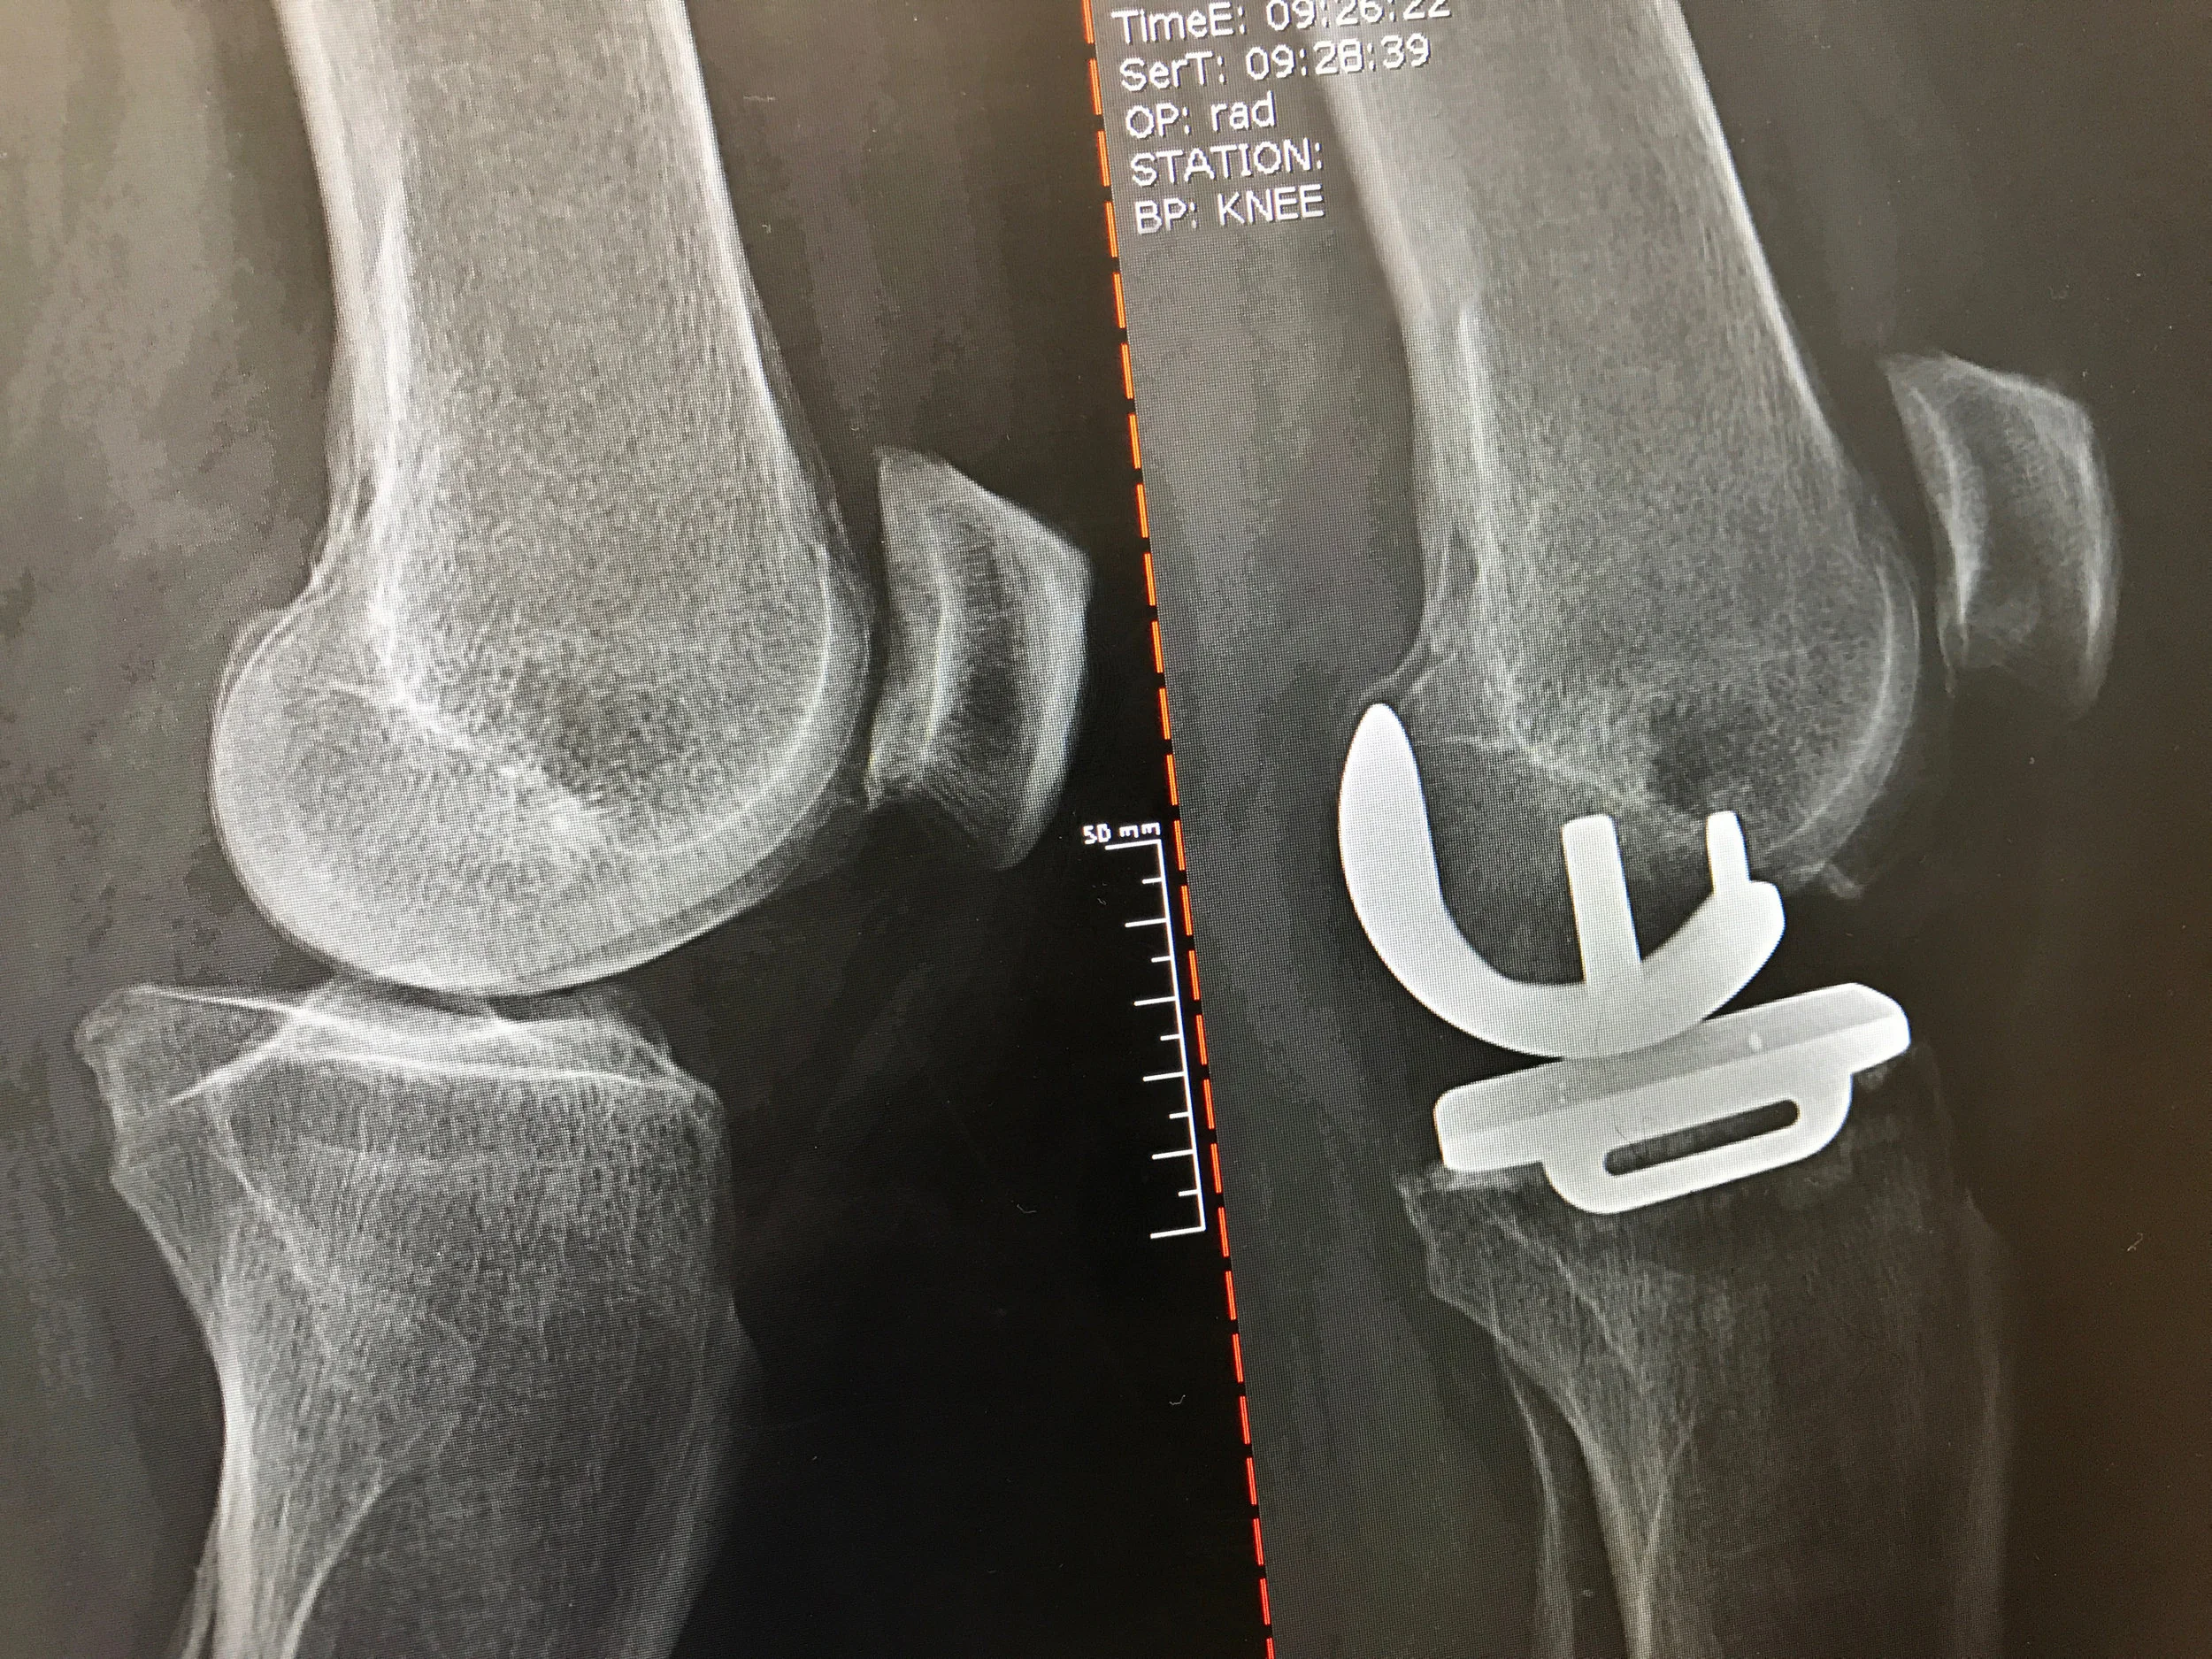

74 year old just 19 days post bilateral partial knee replacement surgery by Dr. Phillip Ludkowski.

Before: Bone on bone arthritis affecting only the medial (inside) compartment

After: Partial Knee Replacement

BIOMET OXFORD PKR